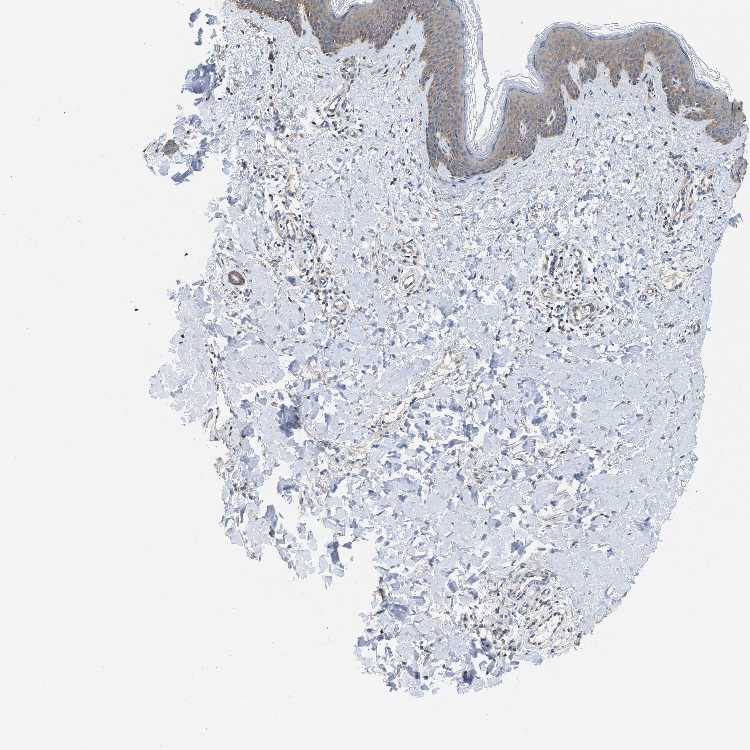

SKIN 1 - Antibody stainingi

Antibody staining in the annotated cell types in the current human tissue is reported as not detected, low, medium, or high, based on conventional immunohistochemistry profiling in selected tissues. This score is based on the combination of the staining intensity and fraction of stained cells.

Each image is clickable and will lead to virtual microscopy that enables deeper exploration of all samples and also displays staining intensity scores, fraction scores and subcellular localization as well as patient and tissue information for each sample.

Antibody HPA029501Antibody CAB019421

Langerhans MediumMedium

Fibroblasts MediumNot detected

Keratinocytes MediumLow

Melanocytes MediumMedium